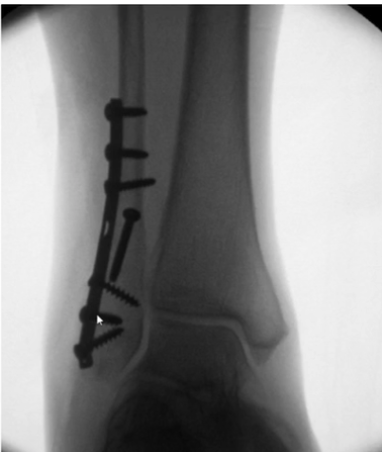

11

What is shown in this X-ray?

Weber’s C fracture with medial malleolus fracture

14

How are Weber’s C fractures managed?

Weber C fractures are managed as unstable, and so surgery is the most common management option

What is the surgical option for ankle fracture?

Surgery in ankle fractures is an open reduction internal fixation (ORIF) operation